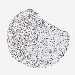

SKIN CANCER - Protein expressioni

A mouse-over function shows sample information and annotation data. Click on an image to view it in a full screen mode. Samples can be filtered based on level of antibody staining by selecting one or several of the following categories: high, medium, low and not detected. The assay and annotation is described here.

Antibody stainingi

Antibody staining in the annotated cell types in the current human tissue is reported as not detected, low, medium, or high, based on conventional immunohistochemistry profiling in selected tissues. This score is based on the combination of the staining intensity and fraction of stained cells.

Each image is clickable and will lead to virtual microscopy that enables deeper exploration of all samples and also displays staining intensity scores, fraction scores and subcellular localization as well as patient and tissue information for each sample.

Antibody HPA019096

Antibody HPA019687

Basal cell carcinoma

Squamous cell carcinoma, NOS

Squamous cell carcinoma, metastatic, NOS